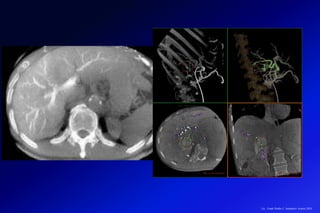

Paciente de 55 años con síndrome metabólico y aumento de enzimas hepáticas de causa no aclarada. (A y B) Secuencias de

desplazamiento químico que muestran una caída de la señal en la secuencia en fase opuesta, por esteatosis. (C) Secuencia

DIXON (IDEAL-IQ), que muestra una proporción de lípidos de 15% comparado con la del bazo (<5%), por esteatosis

moderada/severa. (D) ERM con marcado aumento en la rigidez del tejido hepático (8,2Kpa), hallazgos compatibles con una

esteatohepatítis no alcohólica (EHNA) asociada a fibrosis avanzada (F4).

(AyB) Axial ponderado en T2 y ERM en un paciente en control por Virus Hepatitis

Cronica (VHC). Nótese la distribución heterogénea de la fibrosis, que es avanzada

hacia los segmentos V y VIII (8,5 kPa) y se hace progresivamente menor hacia el

segmento lateral (3,5 kPa) y segmentos posteriores.